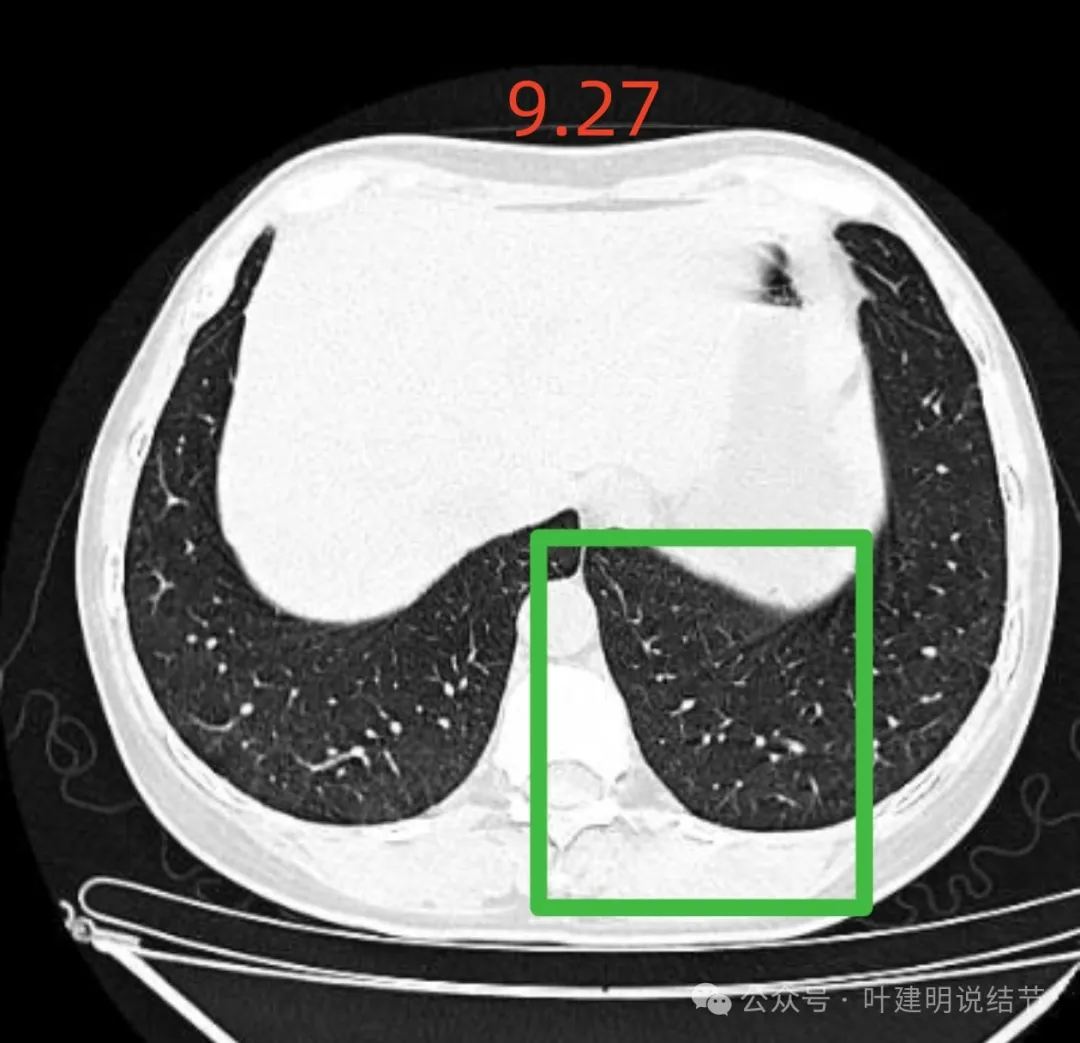

再看2024年9月27号体检时右上后段与左下最明显两处以及实性结节处的影像:

右上与左下混合密度的病灶当时都没有,实性结节是有的。

蓝色的是实性的小结节,缺乏膨胀性,两次检查都有,没有变化,考虑是良性的;红色的这些事10月份检查新增的,这两处比较明显的9月份的时候就是绿色框起来这个区域,当时是没有的。短时间内出现、多发病灶、边缘模糊、轮廓欠清,没有恶性特征,与炎性病变符合。建议查查隐球菌方面的化验,如此结果阳性,请呼吸内科或感染科处理。意见供参考!

9月体检时是说多个小结节,较大的直径7毫米,在236层面。

上图就是236层面,报告说的结节主要的是指左下这处实性的。

肺结节看影像考虑良性还是恶性,从细节上分析影像特征当然是很重要的,但在炎性恢复期有时表现的与肿瘤性质的几乎没有区别,我们自己也在这上面吃过亏,明显混合磨玻璃结节约2厘米,没有随访直接切除后是肺泡上皮增生的,回想或许若术前复查一次,病灶大概明显吸收好转了的。今天分享的这个病例,我认为不可能是恶性的,包括4B这处。原因如下:1、间隔20天,从无到有,并表现为混合磨玻璃密度,若是肿瘤性质没有这么快,不符合磨玻璃肺癌的生物学行为的;2、多发病灶短期内出现,更用炎症能够解释,而用肿瘤不能解释;3、所谓主病灶考虑4B的,整体轮廓虽较清,但瘤肺边界偏模糊,磨玻璃成分密度过低而中间实性成分密度较高,却又缺乏收缩力。病灶紧贴叶间裂,但没有任何牵拉,无胸膜凹陷。其实以上这几点就是炎症性的最重要依据。看肺结节,判断良恶性,不能只纠结于影像表现,要有综合观、全局观,要考虑临床上是否解释得通。